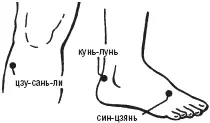

Владимир Васичкин - Лечебные точки организма - снимаем боли в сердце и в области живота

- Название:Лечебные точки организма: снимаем боли в сердце и в области живота

Лечебные точки организма: снимаем боли в сердце и в области живота: краткое содержание, описание и аннотация